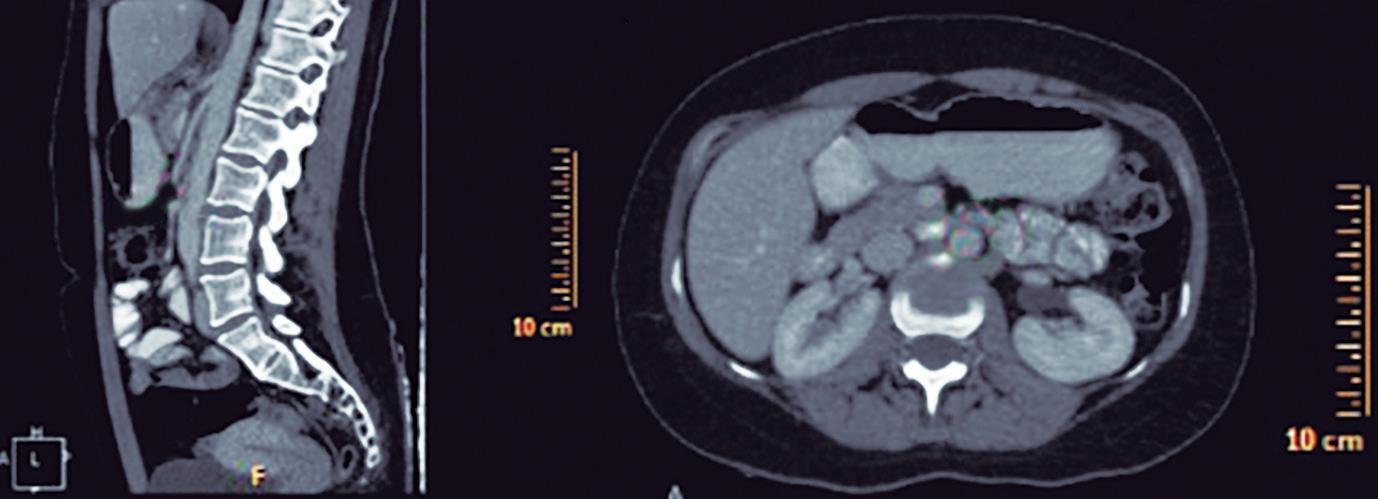

CASOS CLÍNICOS Biopsia guiada por ecoendoscopía como herramienta diagnóstica mínimamente invasiva para metástasis mesorrectal de carcinoma de células claras renales: reporte de caso

Nicole Marie Kahn, Mayra Florencia Defanti, Yanina Gabriela Carlino